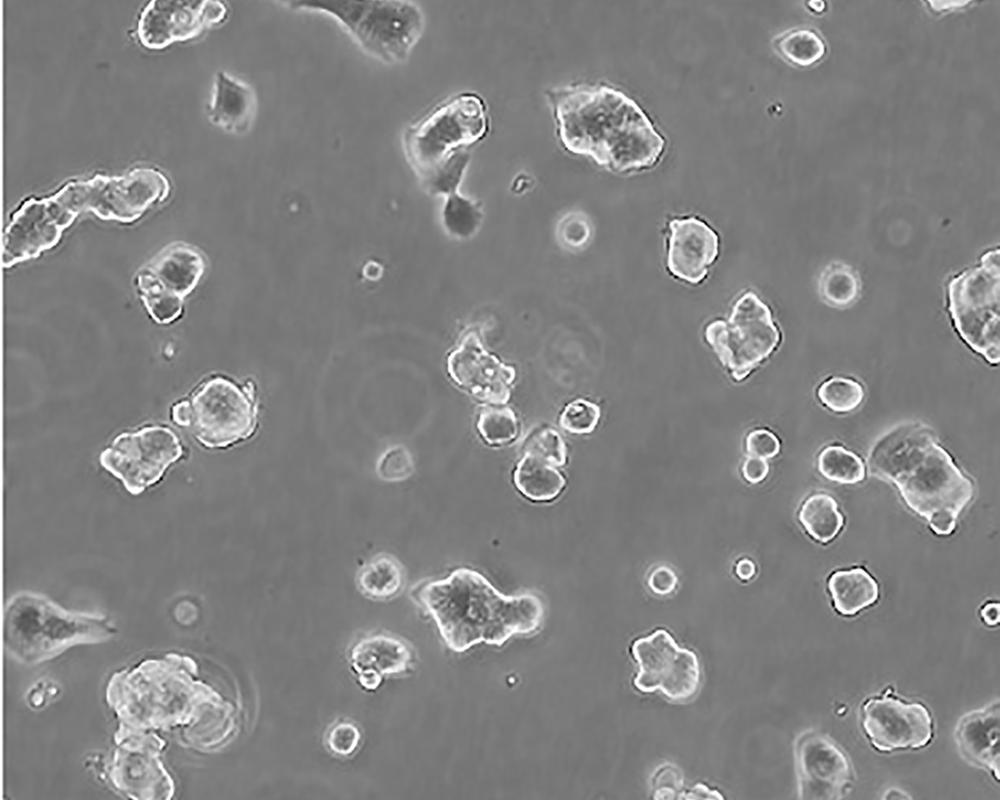

ZR-75-1 [ZR751]

產(chǎn)品名稱 ZR-75-1 [ZR751]

中文名稱 人乳腺癌細胞

組織來源 浸潤性導(dǎo)管癌;腹水轉(zhuǎn)移;女性

生長特性 adherent

形態(tài)特征 epithelial

細胞描述 該細胞產(chǎn)生高水平的黏液素MUC-1 mRNA,低水平的MUC-2 mRNA,但不表達MUC-3基因;表達雌激素受體。